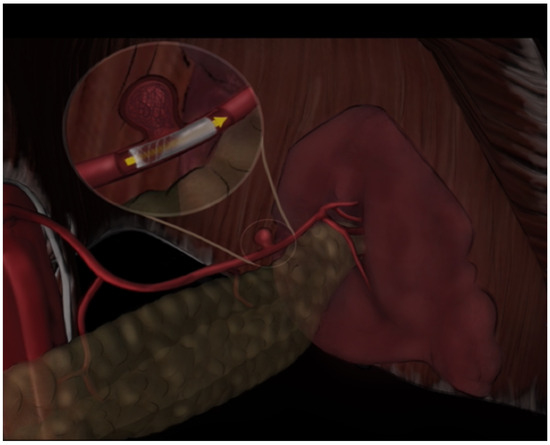

2.3. Interventional Procedure